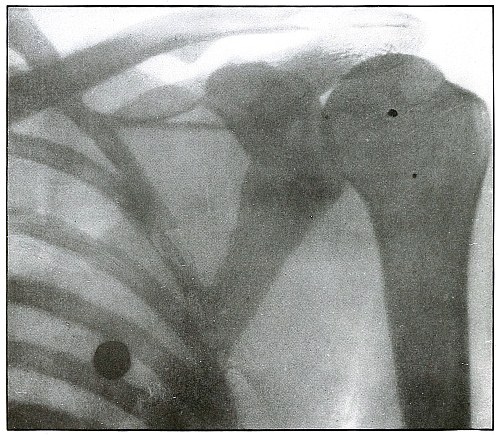

| 82.[Pg 5] |

Gunshot wound, shoulder |

174 |

| 83. |

Gunshot wound, shoulder |

176 |

| 84. |

Gunshot wound, shoulder |

178 |

| 85. |

Gunshot wound, shoulder |

180 |